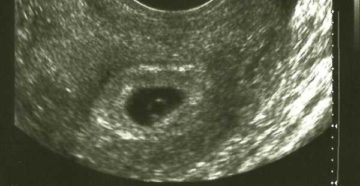

Когда на УЗИ можно увидеть плодное яйцо в матке и почему его бывает не видно…